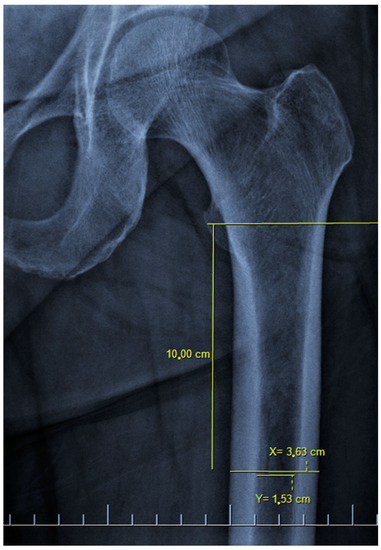

There are also osteoporosis measurements that can be detected by direct radiography, such as the Singh index, Dorr index, cortical thickness index, and canal-to-calcar isthmus ratio. The Singh Index (SI) is a method of measuring osteoporosis determined by detecting trabecular patterns in the proximal femur with plain radiographs. According to the Singh index, osteoporosis is divided into six grades (Grades 1–6). As the grade progresses, the level of osteoporosis decreases; grades 1–3 define definitive osteoporosis (Figure 1) [8]. The Dorr index (DI) is divided into three types according to cortical thickness on proximal femur radiographs (Types A-B-C). As the type progresses, the level of osteoporosis increases (Figure 2) [9,10]. The cortical thickness index (CTI) is measured 10 cm distal to the trochanter minor; its decrease indicates that the cortex is thinning, thus increasing osteoporosis (Figure 3) [9,10]. The canal-to-calcar isthmus ratio (CCR) is calculated as the ratio of the canal diameter 10 cm distal to the trochanter minor to the canal diameter at the calcar on plain radiographs. An increase in this ratio indicates an increase in osteoporosis (Figure 4) [9,10].

Figure 4. The canal-to-calcar ratio (A/B). The diameter of the medulla between the endosteal points 10 cm distal and the mid-lesser trochanteric line is measured (A). Endosteal points located 3 cm distal to the mid-lesser trochanteric line are determined (x). The lines connecting the distal endosteal points with the proximal endosteal points are extended to the mid-lesser trochanteric line and the distance between the lines at this level is measured (B). It was measured as 0.61 (15.3/24.9) on the x-ray of the patient.